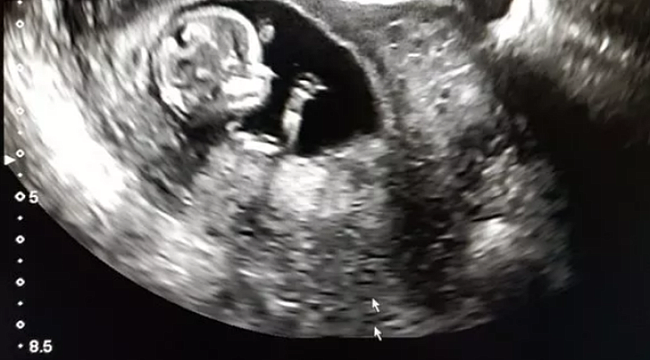

İran'da cinsel organı olmadan doğan bebek tüm dünyayı şaşırttı. Bebeğin annesi yaptığı açıklamada gayet normal bir hamilelik geçirdiğini söyledi. Bebek iki testisi olmasına rağmen penis veya vajinaya sahip olmadan doğdu. Cinsel organı olmadan doğma vakalarının oldukça nadir olarak 30 milyonda bir görüldüğünü belirten doktorlar bebeğe organ yapacaklarını açıkladı. Aphallia adı verilen bu durumun tıbbi literatürde 100'den az vaka belgelendiğini söylendi.

Bebeğin idrarını nasıl yapacağı merak konusu olmuşken anüsünden yaptığı açıklandı. Aphallia, hamileliğin ilk birkaç ayında genital organların rahimde normal şekilde gelişmemesi durumunda ortaya çıkar. Erkeklerin iki penisle doğduğu, diphaliye neden olan benzer bir süreçtir. Radyoloji Vaka Raporları dergisinde vakayı bildiren sağlık görevlileri , çocuğun normal olarak "iyi bir genel durumda" doğduğunu söyledi.YAPILACAK MÜDAHALE TARTIŞILIYOR